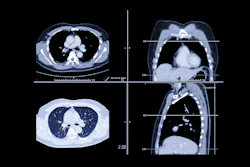

The American College of Radiology (ACR) Foundation has partnered with the Cancer Doesn't Care initiative to launch a fund aimed at expanding lung cancer screening access and early detection for people at high risk who fall outside current screening guidelines.

The Cancer Doesn't Care Fund will support pilot programs, community partnerships, technology development, and policy research, with a focus on uninsured and underserved patients, according to the ACR Foundation. Funding will come from private donors, foundations, industry partners, and grants.

The initiative targets a gap in current U.S. Preventive Services Task Force (USPSTF) lung cancer screening criteria, which are based primarily on age and smoking history, potentially excluding those who have never smoked or smoked minimally, according to the announcement.